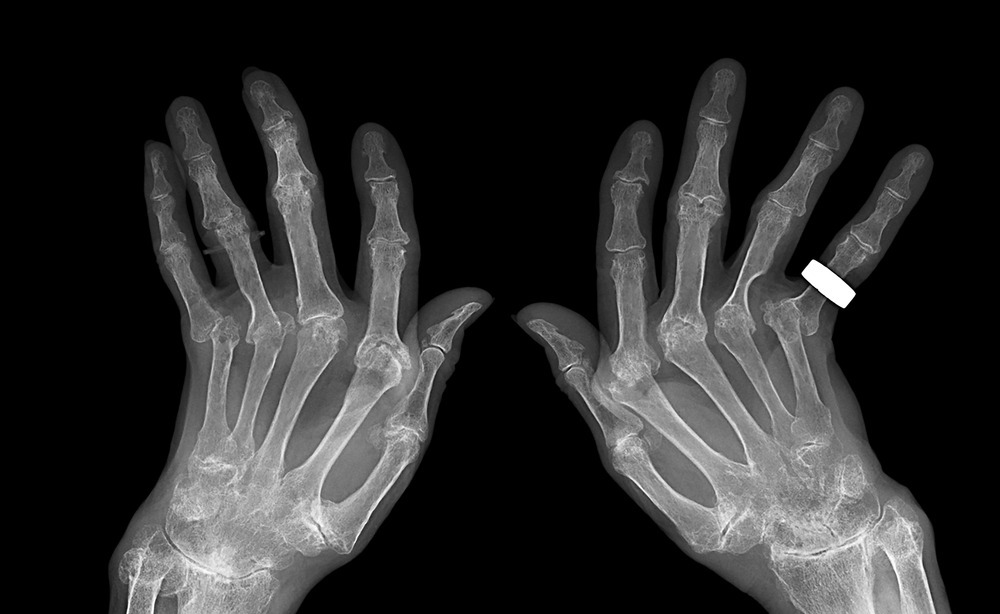

나이가 들어감에 따라 노화가 되면서 자연스럽게 손가락 관절이 퇴행성 변화를 일으킬 수 있습니다. 손가락 연골이 닳고 염증이 생기면서 관절염이 생길 경우 손가락 마디 통증이 발생할 수 있습니다. 마치 나이가 드신 분들이 무릎 관절에 퇴행성 변화로 인한 관절염으로 고생하시는 것과 마찬가지입니다.

이 경우 특히 손가락 첫마디 관절 쪽에서 통증을 느끼는 경우가 많습니다. 퇴행성 관절염으로 인한 손가락 통증 증상을 그대로 방치하여 시간이 오래갈 경우 손가락 관절에 변형이 찾아와 손가락 마디가 튀어 올라올 수 있습니다.